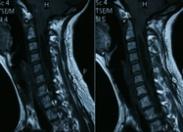

后顱窩型腦積水綜合征即非交通性腦積水,為后顱凹先天畸形,主要為腦脊液儲積至第四腦室囊腫,而發生神經損害癥狀。又稱Dandy-Walker綜合征、Luschka-Magendie孔(第四腦室孔)閉鎖綜合征、第四腦室側孔、中孔閉鎖綜合征等。

- 常見癥狀:頭痛、惡心與嘔吐、煩躁不安、高顱壓綜合征、癱瘓、顱壓增高、步態不穩、眼球震顫、腦積水、智力發育遲緩